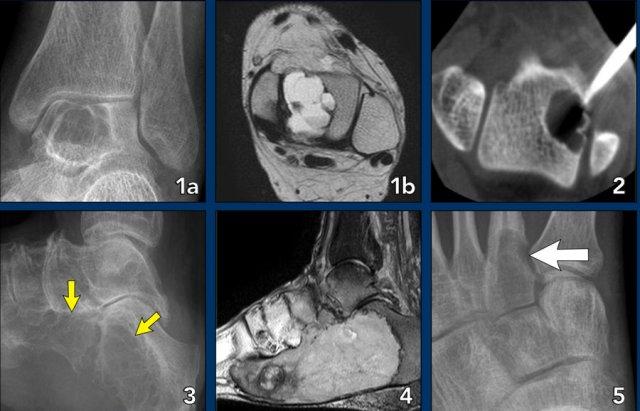

Foot lesions

Here some typical examples of bone tumors in the foot:

- Chondromyxoid fibroma (CMF) in the calcaneus

- Same patient MRI

- CMF in the second metatarsal bone

- Ewing sarcoma in the calcaneus

- Glomus tumor